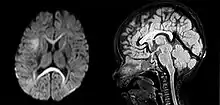

Many people with abnormally large heads or large skulls are healthy, but macrocephaly may be pathological. Pathologic macrocephaly may be due to megalencephaly (enlarged brain), hydrocephalus (abnormally increased cerebrospinal fluid), cranial hyperostosis (bone overgrowth), and other conditions. Pathologic macrocephaly is called "syndromic", when it is associated with any other noteworthy condition, and "nonsyndromic" otherwise. Pathologic macrocephaly may be caused by congenital anatomic abnormalities, genetic conditions, or by environmental events.[2]

In research, cranial height or brain imaging may be used to determine intracranial volume more accurately.[2]